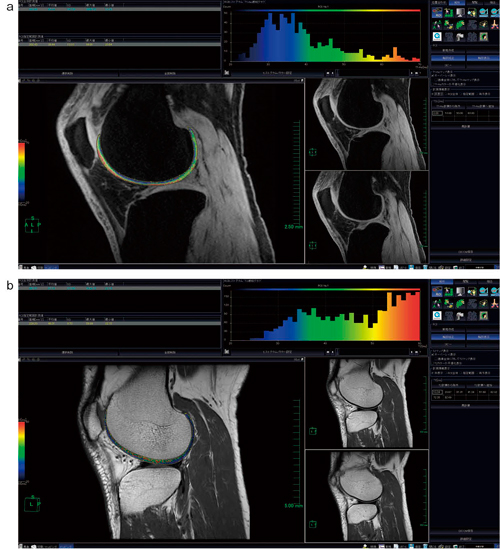

図1 画像解析ソフトウェアのコンソール

a:T1ρマップ b:T2マップ

コンソール上には,関節軟骨の2D/3D緩和時間計算画像,MPR画像,ROI計測値,ROIヒストグラム,緩和グラフ等が表示される。カラーバーの赤色は緩和時間の長い変性部位を,青色は緩和時間の短い健常部位を示している。